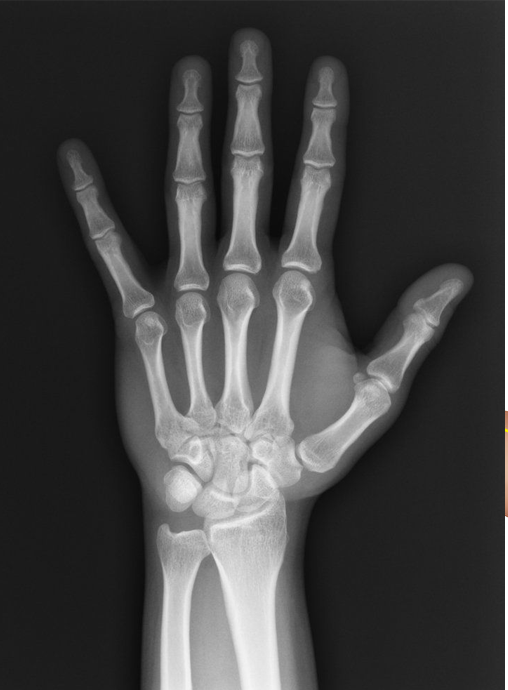

Carpal tunnel syndrome is a condition caused by a compression of nerve in the wrist. Symptoms of carpal tunnel include persistent tingling as well as numbness and radiating pain in the arms and hands. In some cases, you may also experience hand weakness.

Carpal tunnel syndrome is caused by pressure on the median nerve, which runs through a narrow passageway in the wrist called the carpal tunnel. This pressure can be caused by a variety of factors, including repetitive hand movements, arthritis, wrist injury, pregnancy, and others.